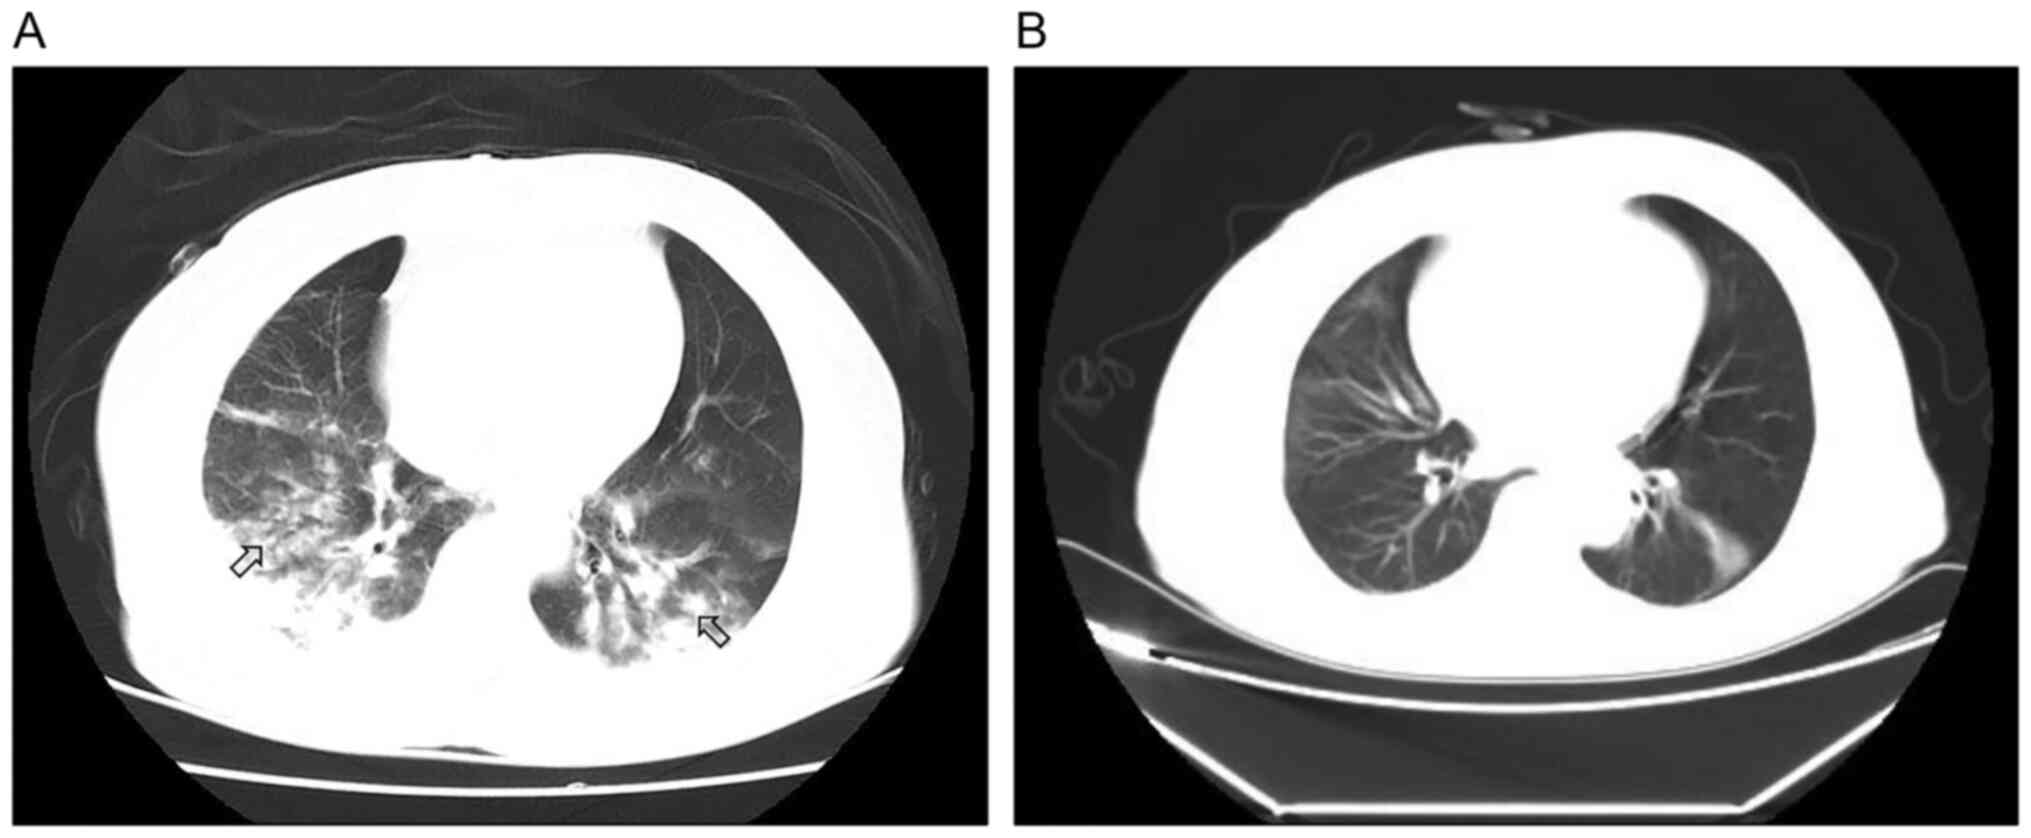

Figure 1

Imaging features of Case 1. (A) Chest CT scan showed diffuse exudative patchy shadows in both lungs. (B) X-rays showed improvement of pulmonary exudative lesions from days 1 to 7 after treatment. The arrows represent the exudative changes in the lungs.

A 67-year-old man accidentally inhaled acid fumes for 1 min before leaving the scene. The patient experienced mild dizziness without any other symptoms one afternoon in April 2021. During approximately 6 h, the patient developed chest tightness and dyspnea. The next day, the patient presented to the Emergency Department of Wuxue People's Hospital (Wuxue, China) complaining of dyspnea after cleaning metal appliances using a nitric-hydrofluoric acid mixture without any protective tools. The patient reported no history of fever or hemoptysis. A chest CT scan showed bilateral diffuse exudative shadows suggestive of pulmonary edema (Fig. 1A). However, the medical capabilities of the hospital were limited and the patient was immediately transferred to the intensive care unit (ICU) of Tongji Hospital (Wuhan, China) for subsequent treatment. The patient experienced tachypnea with the following clinical manifestations: Respiratory rate (RR), 32 breaths/min; body temperature, 36.1˚C; pulse, 105/min; blood pressure (BP), 148/63 mmHg; percutaneous oxygen saturation (SpO2), 90% with consciousness; and inspired oxygen [PaO2(P)/FiO2(F)] ratio, 126. The patient was given oxygen through a facial mask. Dry rales were heard in both lungs. No neck rigidity, arrhythmia or bellyaches were observed. The results of laboratory examinations were as follows: White blood cell (WBC) count, 16.88x109/l; albumin, 25.6 g/l; creatine kinase, 356 U/l; myoglobin, 349.9 ng/ml; calcium, 1.86 mmol/l; phosphorus, 0.66 mmol/l; urea, 10.30 mmol/l; glucose, 11.18 mmol/l; and IL-6, 28.96 pg/ml. Arterial blood gas (ABG) test results showed pH=7.421; oxygen pressure (PaO2), 67 mmHg; carbon dioxide (PaCO2), 35.7 mmHg; arterial oxygen saturations (SaO2), 93%; and P/F, 230 (Table I).

Based on the examination data, the patient was diagnosed with chemical pneumonitis, pulmonary infection and ARDS according to the 2013 Berlin Definition (8). As the patient developed respiratory failure, nasal high-flow oxygen (oxygen flow 55 l/min; oxygen concentration, 60%) was given 4 h later. A new ABG test was performed and the results were as follows: pH, 7.506; PaO2, 138 mm Hg; PaCO2, 31.2 mmHg; and SaO2, 99%. The doctors decided to administer 40 mg of intravenous methylprednisolone and broad-spectrum antibiotics (biapenem and levofloxacin), as referred to in the instructions of the acid cleaning agent, which main components were nitric acid, hydrofluoric acid and surfactants (detailed proportions and concentrations were not described). For ARDS, due to the patient's current nitric acid/hydrofluoric acid inhalation, the drug recommendation was unclear. The patient was treated for 7 days with 0.3 g/day intravenous sivelestat sodium according to the drug indications. The patient presented with severe exudation in both lungs (Fig. 1A) and mild ARDS (nasal high-flow oxygen, P/F 230) without multiple organ dysfunction and met the following criteria for the use of sivelestat sodium: Occurred systemic inflammatory response syndrome (elevated white blood cells and rapid respiratory rate); acute lung injury (P/F >300 mmHg, double lung infiltration shadow on X-ray); and no multiple organ damage of four or more organs. The patient did not have underlying chronic obstructive pulmonary disease (COPD) and other diseases, and high-flow oxygen merely served as a means of respiratory support, rather than as a therapeutic measure. The patients lacked typical infection-related symptoms and was less responsive to antibiotic treatment. At 1 week post-admission to the hospital, the patient's oxygenation had improved and ABG results were pH, 7.662; PaO2, 283 mmHg; PaCO2, 22.6 mmHg; SaO2, 100%; and P/F, 514. Nasal high-flow oxygen was replaced with a nasal catheter. Methylprednisolone and sivelestat sodium were simultaneously discontinued. Radiography revealed significant improvement, as shown in Fig. 1B. The patient was observed in the respiratory department and discharged at 2 weeks post-admission. After 1 month, chest CT and pulmonary function test results were normal.